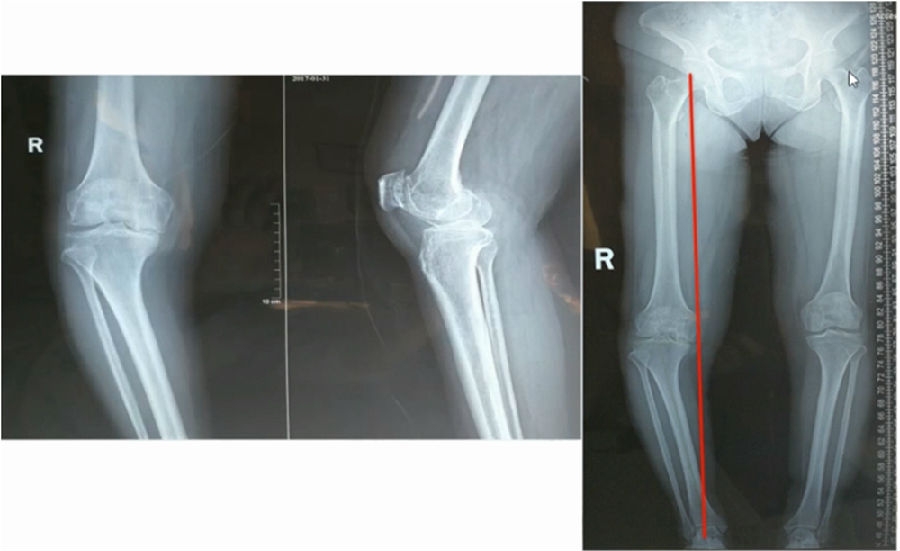

典型病例,女性,35岁,农民,左膝内翻、短缩、内旋。

术前

泰勒外固定架缓慢矫正短缩、内翻、前弓、内旋。

术中

该患者截骨后,做MAD矫正,目标MAD=0。患者术后1个月即达到设计的效果。

术后1个月

典型病例2,男性,52岁,双膝疼痛,低磷佝偻病,复合畸形。

股骨畸形即时矫正,胫骨畸形缓慢矫正。

手术前后对比

手术前后外观